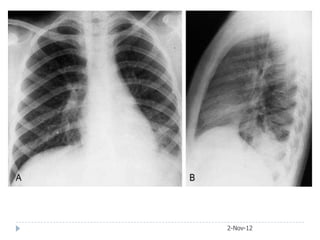

2-Nov-12

• #40 This x-ray shows a large lobar density in the right upper lobe with some area of incomplete consolidation in the density. The lower end of this opacity is bulging and the horizontal fissure is displaced downward.The lateral confirms large right upper lobe pneumonia with a bulging fissure seen in a densely consolidated lobe due to klebsiella pneumonia.